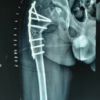

A 53-year-old male came to SGT hospital with gross deformity of the right thigh of 14 years duration and pain over the medial side of the knee for 6 months with a VAS score of 7. The patient gives a history of a road traffic accident in December 1991, in which he sustained a right femur shaft fracture, for which he was operated on with a K-nail. He gives a history of re-trauma after 2 months of surgery in which he sustained an injury on the operated side. He did not undergo any surgery 2nd time. The patient gives a history of gradual increase in deformity of the right thigh for a few years following re-trauma. Now, the patient came with a complaint of pain over the medial side of the knee joint for the last 6 months and deformity for 14 years. No other significant history or any comorbidities. Clinical assessment reveals a short limb gait and limb length discrepancy of 3 cm. He had gross varus deformity of the right thigh with right knee medial joint line tenderness. There was no significant muscle atrophy. He had a full knee range of motion and was able to squat and sit on a crossed leg. Spine, bilateral hip, and ipsilateral ankle examination findings were normal. Plain radiograph in two views demonstrated gross varus deformity of 23⁰ of the right middle third femur following malunion with broken K-nail at two places in situ (Fig. 1) with Kellgren–Lawrence Grade 3 knee osteoarthritis (Fig. 2). The deformity angle was 23°.

The apex of the deformity was at the middle third of the right femur. The lateral view of the femur revealed anterior bowing of the femur in the sagittal plane (Fig. 3). Malunited right femur shaft fracture with broken K-nail in situ with 3 cm shortening with secondary degenerative arthritis medial compartment right knee. Osteotomy at two levels (Fig. 4), realigning implant removal and internal fixation with interlocking nailing.